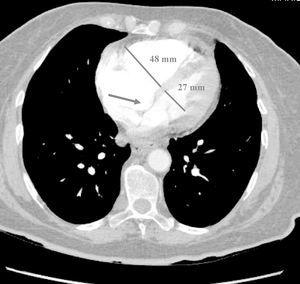

Paciente de 73 años de edad que ingresa en la Unidad de Cuidados Críticos por síncope e hipotensión arterial refractaria a la administración de fluidos intravenosos. En la tomografía axial computarizada (TAC) torácica helicoidal realizada, con protocolo de tromboembolismo pulmonar, se observan signos de embolismo pulmonar extenso con afectación de arterias pulmonares principales y lobares de ambos hemitórax. Igualmente se aprecian signos de sobrecarga ventricular derecha e hipertensión pulmonar. En la figura 1 se observa la dilatación del ventrículo derecho, con índice de diámetro de ventrículo derecho/diámetro de ventrículo izquierdo mayor de 1,5; la flecha indica el abombamiento del septo inter-auricular. En la figura 2 se aprecia, además, reflujo de contraste intravenoso a la vena cava inferior, que se encuentra dilatada. Por tanto, los hallazgos tomográficos podrían servir para valorar de forma indirecta la sobrecarga aguda del ventrículo derecho, secundaria a un tromboembolismo pulmonar.

Figura 1.